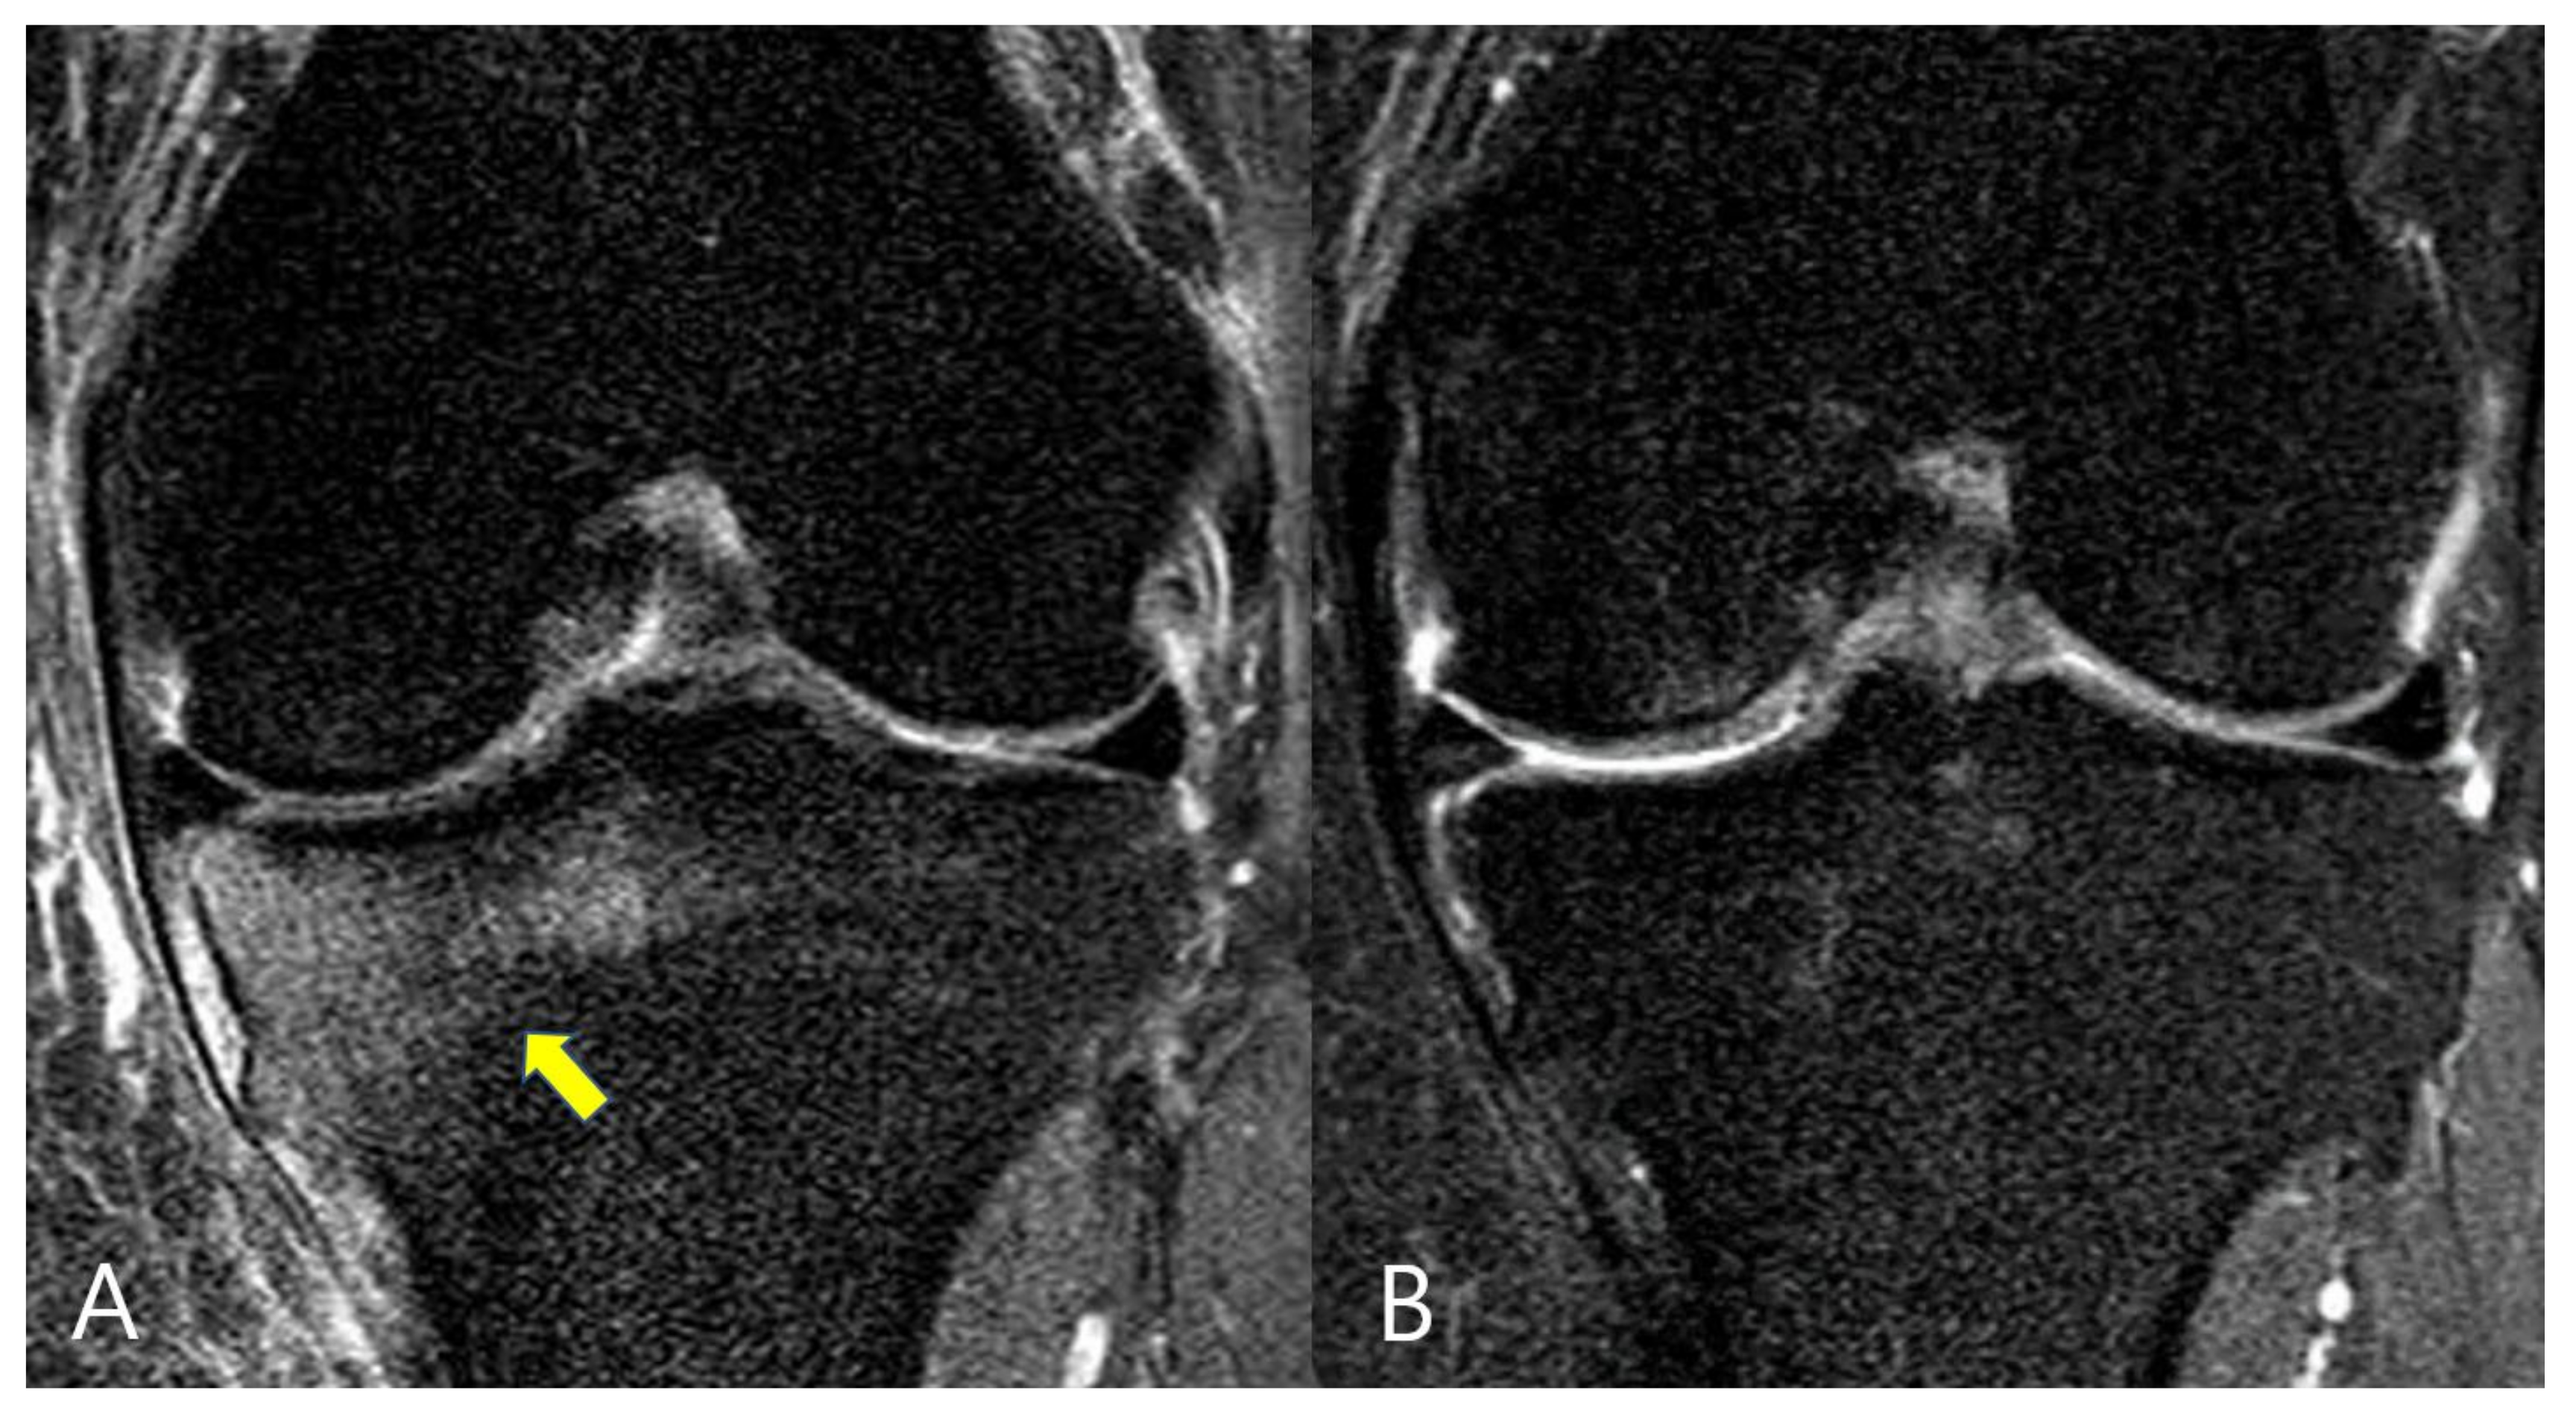

2.2. Evaluation of Bone Marrow Lesions